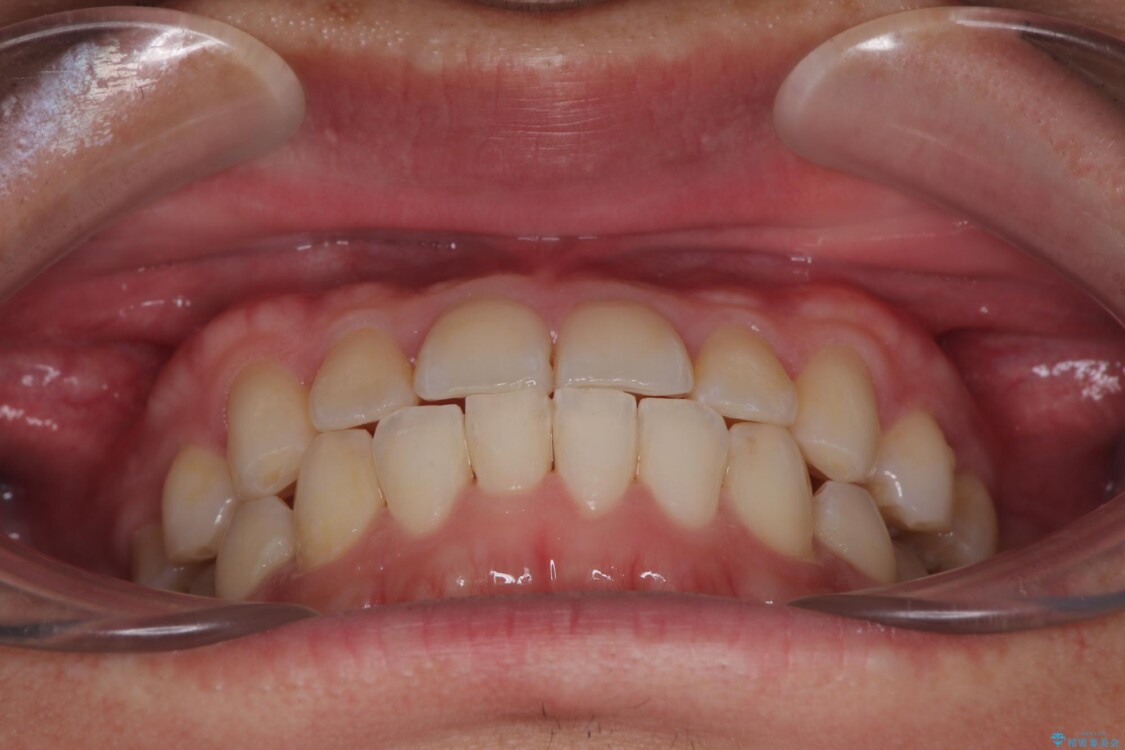

**前歯のデコボコ(叢生)**が整い、歯列全体が美しく改善

シザーズバイトの奥歯も正常なかみ合わせに改善

捻転歯も回転が修正され、全体的に清掃性・咀嚼効率が向上

患者様にも「大人になってから矯正を始めることに不安もありましたが、思っていたよりも短期間で治療が終わって本当にうれしいです。前歯のガタガタも気にならなくなり、笑うことに自信が持てるようになりました!」と喜んでいただけました。

治療後

• 前歯のガタガタ・奥歯のかみ合わせ(シザーズバイト)を改善|1年半で完了したメタルブラケット矯正 治療後画像